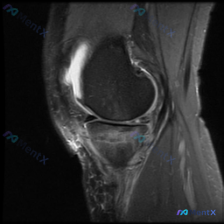

给大家分享一个很有启发的膝关节MRI读片病例,临床关注点是半月板异常,读完片发现其实核心问题不在这儿,整理一下完整分析思路。 病例影像基本信息 这是一份膝关节矢状位T2加权MRI(压脂序列),我们先整理所有客观发现: 1. 关节内结构:半月板形态完整,呈典型低信号三角表现,未见贯穿性高信号,边缘光滑...

看到一份很有启发的膝关节MRI病例,初始提示是「半月板异常」,但读片后的发现和一开始的方向完全不一样,整理一下完整分析思路跟大家分享。 一、病例影像基础信息 这是膝关节MRI矢状位T2加权图像,我们先整理所有客观发现: 1. 骨骼关节:股骨远端、胫骨近端、髌骨骨皮质完整,无明显骨折或骨质破坏,髌骨与...

病例读片分享:临床怀疑半月板异常,MRI却只看到髌周病变 基本影像信息 提供的影像为膝盖MRI-T2序列矢状位,切面位于膝关节前部髌股关节区域,图像存在一定截断伪影,未显示后交叉韧带及大部分后侧软组织结构。 影像核心发现 整理一下客观观察到的异常: 1. 髌前皮下软组织水肿:髌骨前方及皮下组织层可见...

看到这份有意思的病例,主诉是提示半月板异常的膝关节MRI,整理了完整的读片思路和分析,分享给大家。 一、影像基础信息 这是一幅膝关节MRI T2加权矢状位图像,我们先确认基础信息: - 成像序列符合T2WI特征:液体高信号、软骨中等信号、脂肪低信号、骨皮质及韧带低信号 - 切面展示膝关节前部结构:髌...